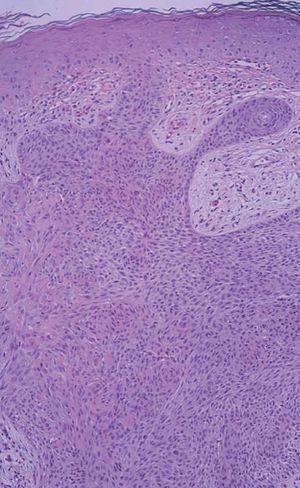

Con el diagnóstico clínico de carcinoma basocelular se realizó una biopsia incisional, que puso de manifiesto una proliferación de células basaloides dispuestas en empalizada originadas a nivel de la epidermis y que infiltraban la dermis (fig. 2). Los estudios complementarios realizados (hemograma, bioquímica, coagulación) fueron compatibles con la normalidad.

Fig. 2.--Células basalioides en grupos dispuestos periféricamente en empalizada, que nacen de la membrana basal epidérmica e infiltran dermis (H-E, x10).